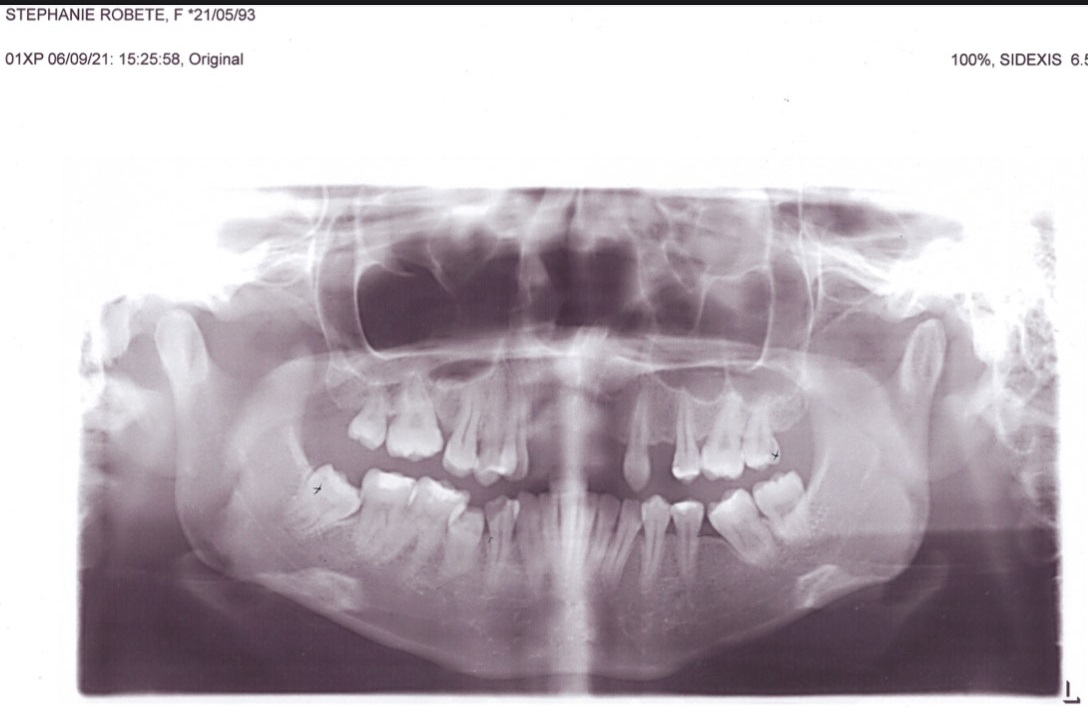

Edit Record Check our patient data records. Add patient information Patient Info Profile picture Last Name First Name Middle Name Birthdate Age Street Barangay City Country Zip Code Contact number Email Procedure 09/08/21- LC 16 occ/ 26 occ/ 25 distal/ 44 DOB+CAOH/ exo 28 with suture and laser 09/18/21 suture removal 28 10/11/21- odontectomy 48 4 sutures/ Rx Co amoxiclav 625mg 01/04/25 OP deep cleaning LC #46 O, M Caoh xray Flexite Denture 5 units upper shade A3 01/14/25 trial 01/25/25 install denture 02/01/25 install brace L 14 Niti L roth 0.22 slot 03/14/25 RW #33 same wire 04/11/25 Adj 16 NiTI L 05/20/25 lingual button #45 18 NITI L 06/10/25 adj 18 niti L nxt visit reattached lingual button #45 07/25/25 same wire RW #45 w/ chain to #46 LC #31 M 08/22/25 adj 16 SS L 11/20/25 adj same wire 12/18/25 16 & 18 SS lower - double wiring Button #44 01/7/26- same wire. IPR 44, 45 derotate 45 1/23/26 adj same wire L, button on #46 chain #33 to 35 2/5/26 adj same wire 3/5/26 adj same wire 04/08/26 adjustment re-attached button 04/29/26 adjustment attach 2 button #44|#45 File stephanie_panoramic.jpg File 2 robete48.jpg File 3 robete48-2.jpg File 4 File 5 File 6 File 7 File 8 File 9 File 10 File 11 File 12 File 13 File 14 File 15 File 16 File 17 File 18 File 19 File 20 Retain Record Retain Record Yes No Save Your Changes